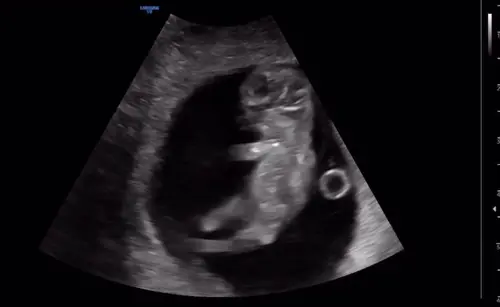

Hier wekenlang bij elke echo vanaf 20 weken (door complicaties elke week echo gehad) lag meneer met z'n voeten tegen z'n voorhoofd aan en z'n armen om z'n benen geslagen haha. Zelfde praktijken liggend in de box nu